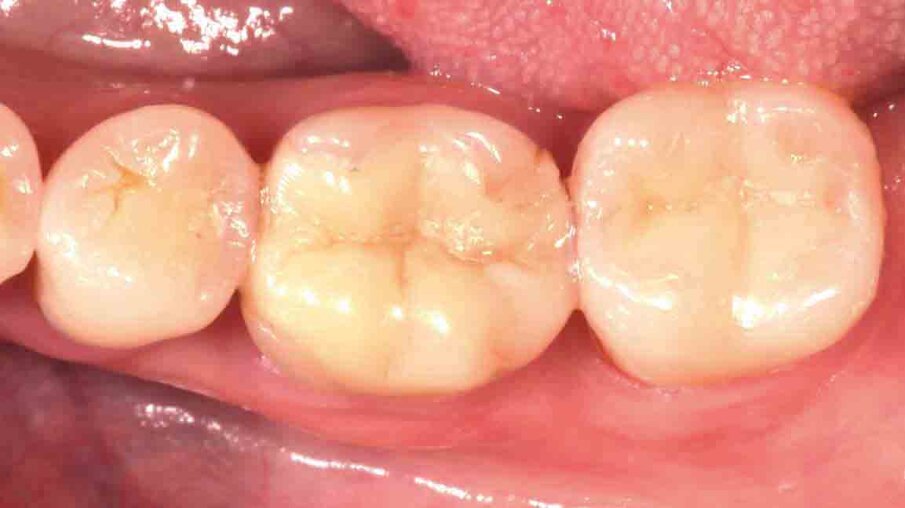

Fig. 5: One week after the preparation procedure, healthy soft tissue conditions are obtained. They lay the foundation for a high-quality precision impression.

Fig. 6: In order to allow for a detailed capture of the preparation margin, the gingival tissues are retracted using the double-cord technique. Alternatively, a single cord may be applied in combination with 3M™ Astringent Retraction Paste.

Fig. 7: Monophase impression taken with 3M™ Impregum™ Penta™ Soft Medium Body Polyether Impression Material. A very detailed representation of the preparation margin is obtained with this simple technique.